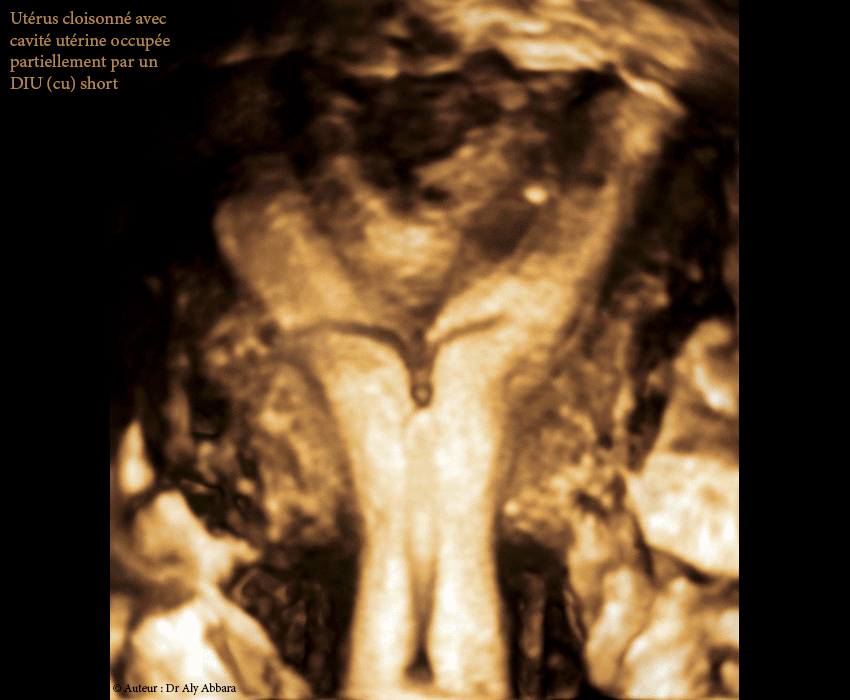

Positionnement d'un DIU au cuivre dans la cavité d'un utérus malformé, cloisonné

• Images échographiques montrant, sur une coupe frontale (3D) puis une coupe sagittale médiane (2D), le positionnement d'un DIU(Cu) short (en T) dans la cavité utérine d'un utérus malformé cloisonné partiel corporéal (U2a = utérus extérieurement normal avec un septum fundique interne médiane supérieur à 50 % de l'épaisseur de la paroi utérine).

Il s'agit d'une cloison utérine corporéale verticale médiane méconnue au moment de la pose de ce DIU (stérilet) chez une femme âgée de 25 ans, nulligeste.

• Ces images expliquent le positionnement bas du DIU dans la moitié inférieure de la cavité du corps utérin tout en laissant les deux cornes utérines (formées par la présence de la cloison) hors contact avec les différentes composantes du DIU (la tige verticale cuivrée et les deux bras horizontaux).

• Cette occupation partielle de la cavité utérine par le DIU peut comporter probablement le risque de réduire son effet contraceptif par son manque de contact avec l'endomètre et par une diffusion insuffisante du cuivre dans la cavité utérine.